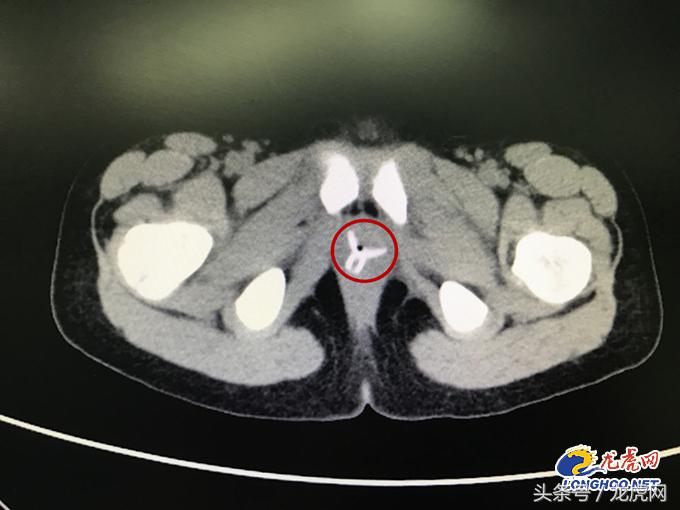

妈妈在南京市儿童医院泌尿外科门诊找到了葛征副主任医师,葛主任表示,如果不是“阴道炎”,那么一方面要考虑其他阴道疾病,另一方面就是阴道异物,都有可能导致类似症状,建议通过CT平扫明确病因。当天,CT结果出来后医生和家长惊讶地发现,楚楚的阴道内有一个“Y形”的异物,这应该就是“会阴红肿,分泌物增多”的罪魁祸首。

葛主任决定将楚楚收入病房,通过膀胱镜手术取出异物,同时建议家长尽量在术前弄清异物的质地和进入时间,以保证手术的安全性。终于,在家长的再三询问下,楚楚想起去年暑假,自己和小伙伴玩“医生病人过家家”游戏时,小伙伴曾将一个小吸盘从她的*体下**塞入,但她事后并没有告诉家人。也就是说,异物已经在楚楚体内待了将近一年。

入院完成相关检查后,泌尿外科郭云飞主任医师亲自操刀,在全麻下给楚楚施行了膀胱镜取异物手术。术中,郭主任发现楚楚的整个阴道都存在红肿,还有炎性肉芽肿,异物大约位于阴道1/3—1/2处。郭主任小心翼翼地将异物逐渐拉出,在无阴道出血、无伤口的情况下完整取出了一个直径约3公分的橡胶吸盘。